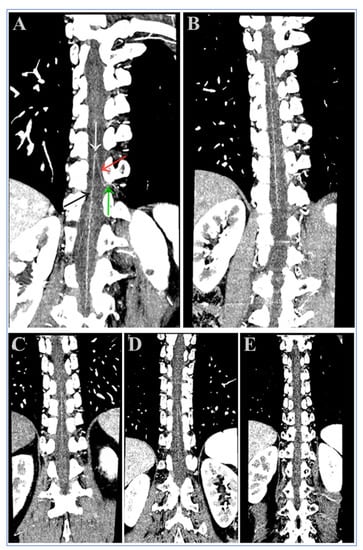

| Groups | Image Reconstruction Methods | Visualization Scores of the Adamkiewicz Arteries | Hairpin Curve | Branching Level | ||||

|---|---|---|---|---|---|---|---|---|

| 1 = Poor | 2 = Fair | 3 = Good | 4 = Fine | 5 = Excellent | ||||

| Group B | 120 kV FBP | 12 (24.0%) | 14 (28.0%) | 11 (22.0%) | 9 (18.0%) | 4 (8.0%) | 38 (76.0%) | 24 (48.0%) |

| Group A | 100 kV FBP | 5 (10.0%) | 9 (18.0%) | 16 (32.0%) | 12 (24.0%) | 8 (16.0%) | 45 (90.0%) | 36 (72.0%) |

| 100 kV ASIR-V 60% | 3 (6.0%) | 5 (10.0%) | 10 (20.0%) | 19 (38.0%) | 13 (26.0%) | 47 (94.0%) | 42 (84.0%) | |

| 100 kV ASIR-V 70% | 3 (6.0%) | 4 (8.0%) | 10 (20.0%) | 20 (40.0%) | 13 (26.0%) | 47 (94.0%) | 43 (86.0%) | |

| 100 kV ASIR-V 80% | 2 (4.0%) | 3 (6.0%) | 9 (18.0%) | 22 (44.0%) | 14 (28.0%) | 48 (96.0%) | 45 (90.0%) | |

| 100 kV ASIR-V 90% | 2 (4.0%) | 3 (6.0%) | 7 (14.0%) | 24 (48.0%) | 14 (28.0%) | 48 (96.0%) | 45 (90.0%) | |

| 100 kV ASIR-V 100% | 2 (4.0%) | 3 (6.0%) | 6 (12.0%) | 24 (48.0%) | 15 (30.0%) | 48 (96.0%) | 45 (90.0%) | |